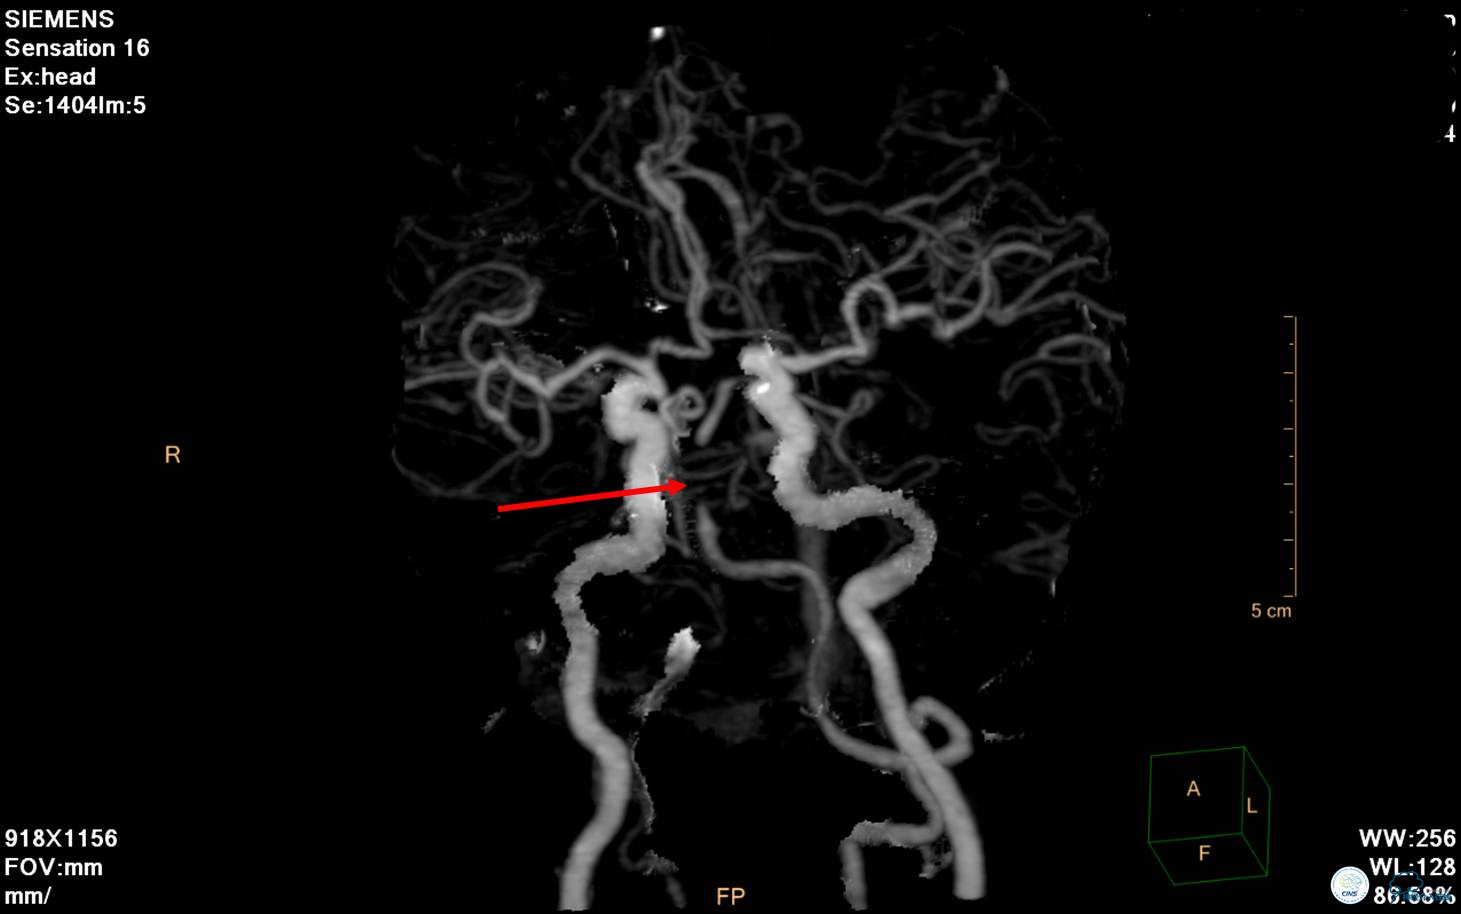

▼ CTA提示基底动脉中段闭塞。

▼ CTA:右侧后交通动脉开放、左侧大脑后P2段闭塞。